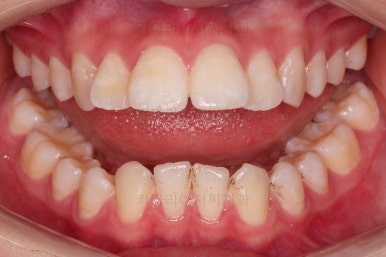

마찬가지로 초진 시 얼굴 모습인데요.

웃을 때 윗니는 매우 튀어나오고 뻗쳐 보이고요.

매우 특징적인 패턴이 아랫입술 ~ 턱끝까지 이어지는 부위가 움푹 들어가 있죠.

과개교합이신 분들은 아랫입술이 해당 부위로 말려들어가면서 저렇게 아랫입술 아래가 움푹 들어가는데요.

심한 경우에는 영구적으로 주름이 잡혀 버리는 상황도 생깁니다.

심미적으로 좋지 못하죠.

아랫니도 가능한 앞으로 빼주면서 아랫입술 아래의 푹 들어간 주름을 점점 개선해 줍니다.

얼굴모습에서도 발치교정이지 윗입술이 많이 들어가지 않게끔 아랫니를 최대한 앞으로 빼둔 상태여서 윗ㅇ입술은 양호하며, 아랫입술은 아래쪽에 깊게 패여있던 주름도 많이 퍼졌습니다.